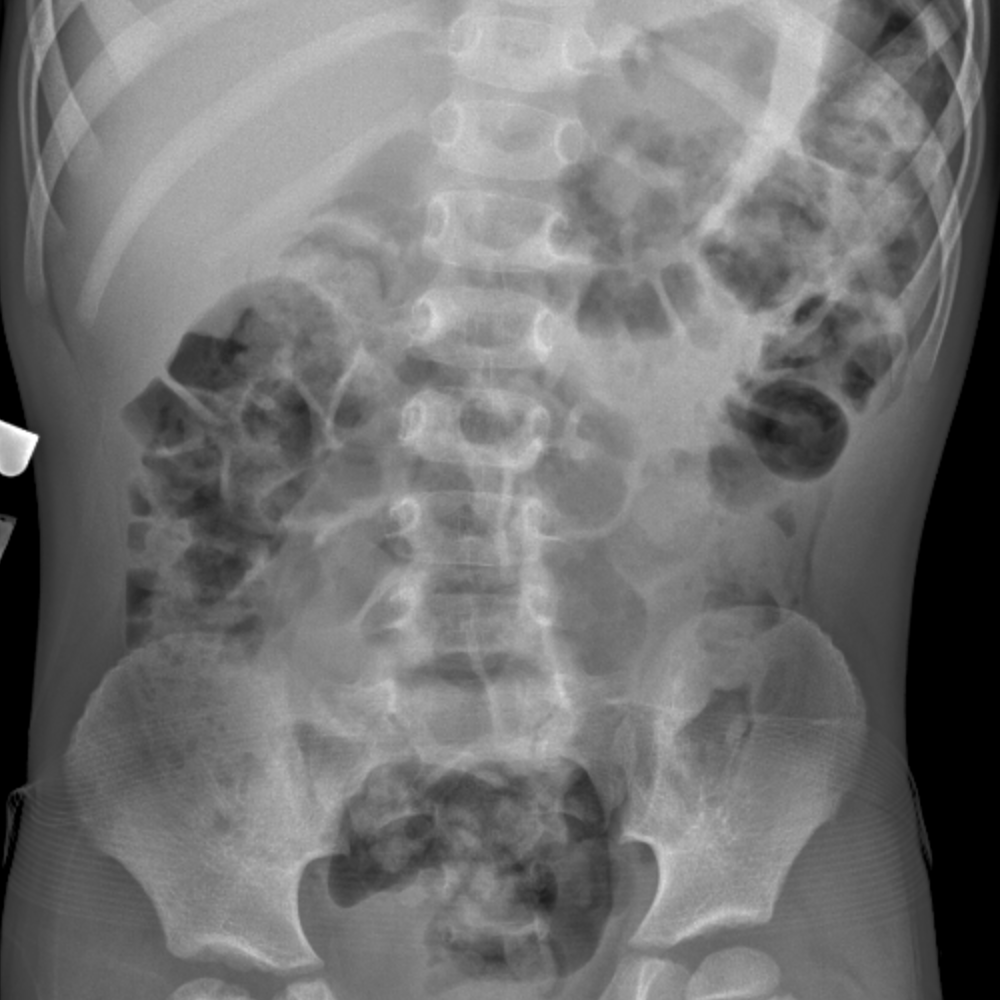

30+ Nonobstructive Bowel Gas Pattern

Web A non specific non obstructive pattern means that there is an abnormal.

. Our Health Experts Researched And Found The Top 5 Best Digestive Enzymes Supplements. Web Case 30 Findings Nonobstructive bowel gas pattern Increased density throughout the. Ad Learn about it.

Pass it rectally which. The Only Noninvasive Colon Cancer Test That Can Detect Both Altered DNA Blood In Stool. Web Non obstructive bowel pattern on abdominal X-ray means no evidence of.